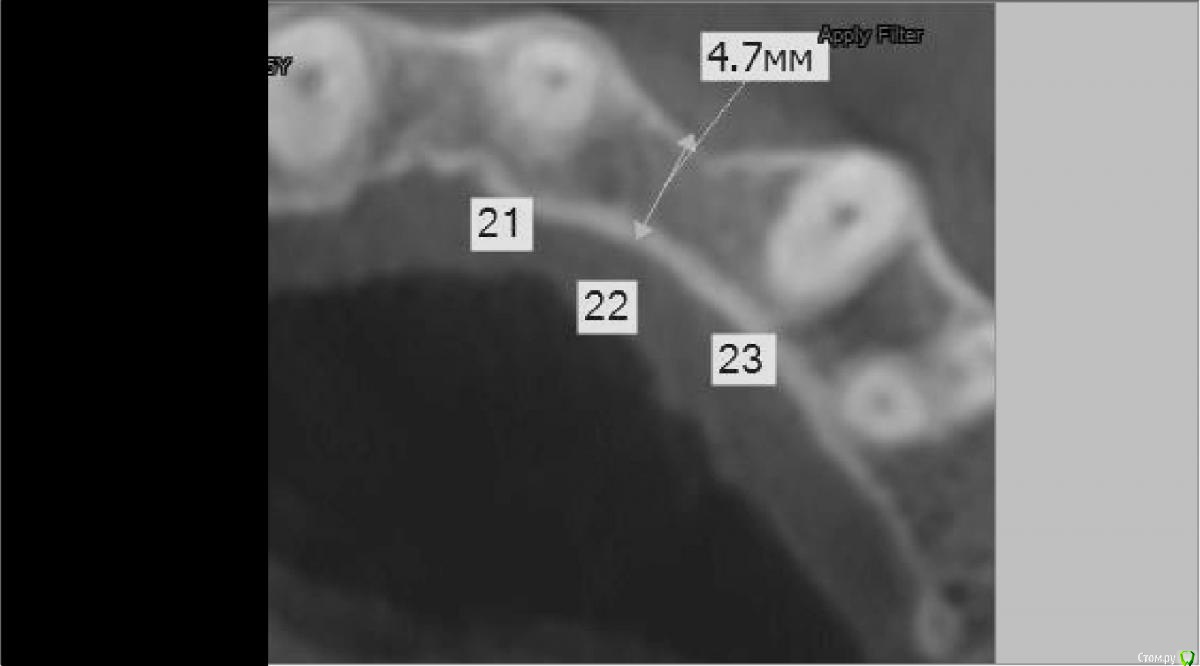

red_butler Опубликовано 14 ноября, 2015 Поделиться Опубликовано 14 ноября, 2015 Бывают же методики устаревшие , изжившие себя, превышающие риск над пользой, может расщепление из таких?Снимок не совсем информативен, не понятно на какой высоте эти срезы. Но в подобной ситуации, я бы поставил импланти делал НКР или расщепление с НКР, но не костный блок. P. S. Личные данные со снимков лучше убирать. Ссылка на комментарий

dsfksdkf Опубликовано 14 ноября, 2015 Автор Поделиться Опубликовано 14 ноября, 2015 Снимок не совсем информативен, не понятно на какой высоте эти срезы. Но в подобной ситуации, я бы поставил импланти делал НКР или расщепление с НКР, но не костный блок. P. S. Личные данные со снимков лучше убирать.Скажите пожалуйста что такое НКР? может вот этот снимок подойдет Ссылка на комментарий

red_butler Опубликовано 14 ноября, 2015 Поделиться Опубликовано 14 ноября, 2015 Скажите пожалуйста что такое НКР? может вот этот снимок подойдетНаправленная костная регенерация.Да с этим снимком все встало на свои места.Технику костной пластики выбирает врач, Вы выбираете врача. 1 Ссылка на комментарий

dsfksdkf Опубликовано 2 декабря, 2015 Автор Поделиться Опубликовано 2 декабря, 2015 (изменено) я скорее всего вообще бы не наращивал кость в данной ситуации.тоже не хочется наращивать, но 1 врач говорит что имплант должно окружать как минимум 1 мм, а лучше 2мм, что кость питалась и не рассасывалась, а у меня не хватает. То есть 3, 5 мм имплант и 4, 7 мм кость . Если это так ( так ли это?),то мне бы не хотелось потерять в будущем имплант или чтобы он оголился и пр. негативные последствия... Изменено 2 декабря, 2015 пользователем dsfksdkf Ссылка на комментарий